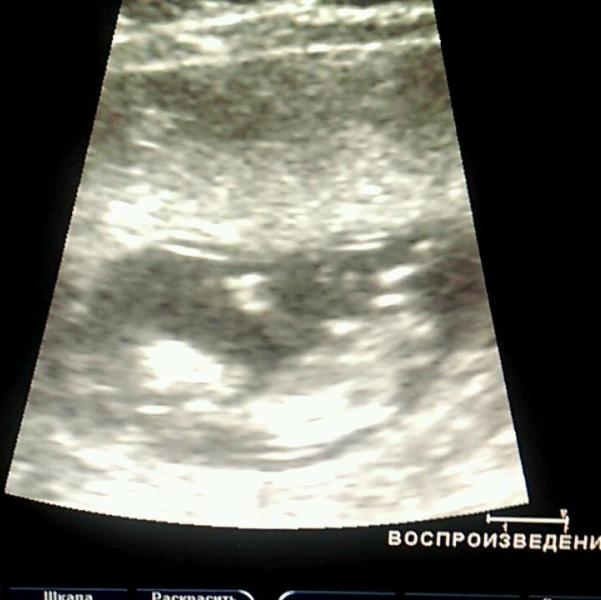

Сегодня у нас 12 недель!👑 )))Сегодня ездили с мамулей сдавать кровушку на инфекциии🙈тут нам предложили скрининг!Хоть и планировали в 14 недель но согласились😊) По узи у нас Малыш здоровенький и хорошо развивается✅! Правда на экране было видно, что мы разбудили его🔆))) Кровоток у нас хороший) Сердцебиение 143💓!( интересно это мальчик или девочка?!)